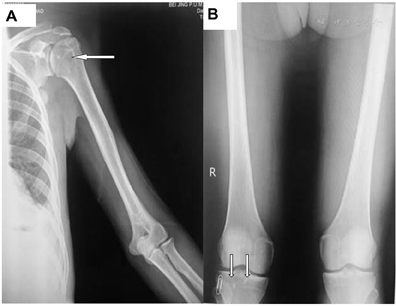

体格检查:血压130/80 mmHg(1 mmHg=0.133 kPa),体重指数26.12 kg/m2,营养中等,神志清楚。颜面、双手及双上臂皮肤变黑、增厚,双上臂多毛表现(图2)。双眼睑水肿,颈部及后背可见散在皮赘。甲状腺不大,双肺呼吸音低,右侧为著。心率80次/min,律齐,各瓣膜听诊区未闻及杂音。腹膨隆,肝肋下5 cm,脾肋下6 cm。移动性浊音阴性。四肢皮肤多毛,双侧乳晕色素沉着。双下肢可凹性水肿。下肢浅感觉正常,双侧膝腱反射对称。影像学资料:心脏彩超示全心增大,轻度二尖瓣关闭不全,轻度三尖瓣关闭不全,左室舒张功能减低,升主动脉增宽,中度肺高压,主肺动脉增宽,少量心包积液。X线片示左侧肱骨头、右侧股骨内侧髁、右侧胫骨头及右侧股骨干骺端高密度影(图3A、图3B)。

注:左侧肱骨头(A)和右侧胫骨头(B)显示高密度影(箭头所指),提示骨质硬化改变